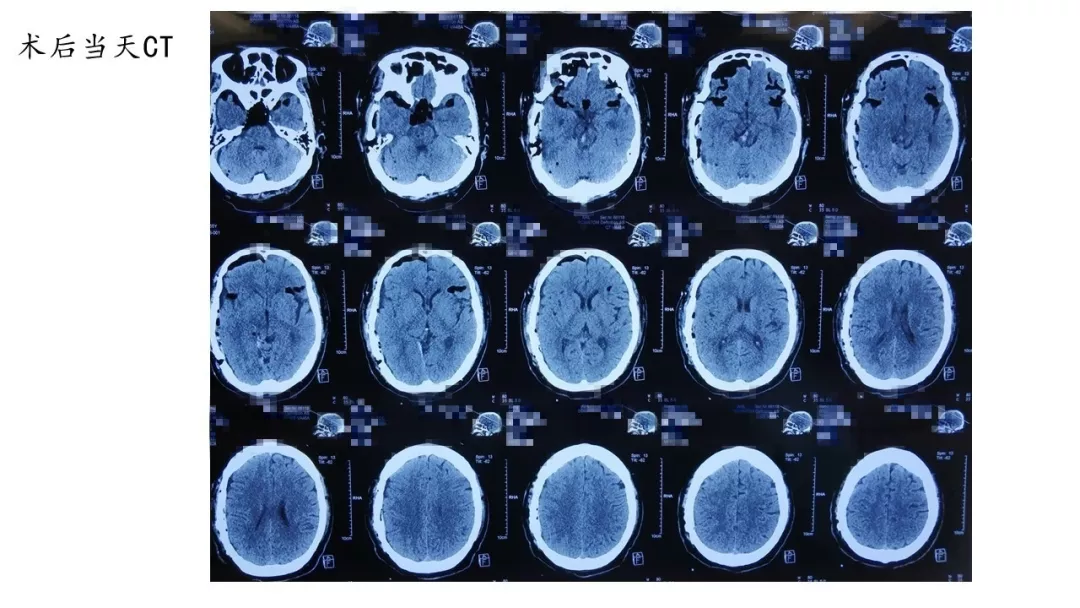

夹闭过程中,动脉瘤瘤颈撕裂,经多次尝试各种型号动脉瘤夹塑形均不满意。最后采用组合动脉瘤夹塑形+瘤颈破口棉片包裹方式夹闭动脉瘤(见链接视频),效果满意,颈内动脉通畅无狭窄,也无动脉瘤残留。术后病人恢复良好出院。